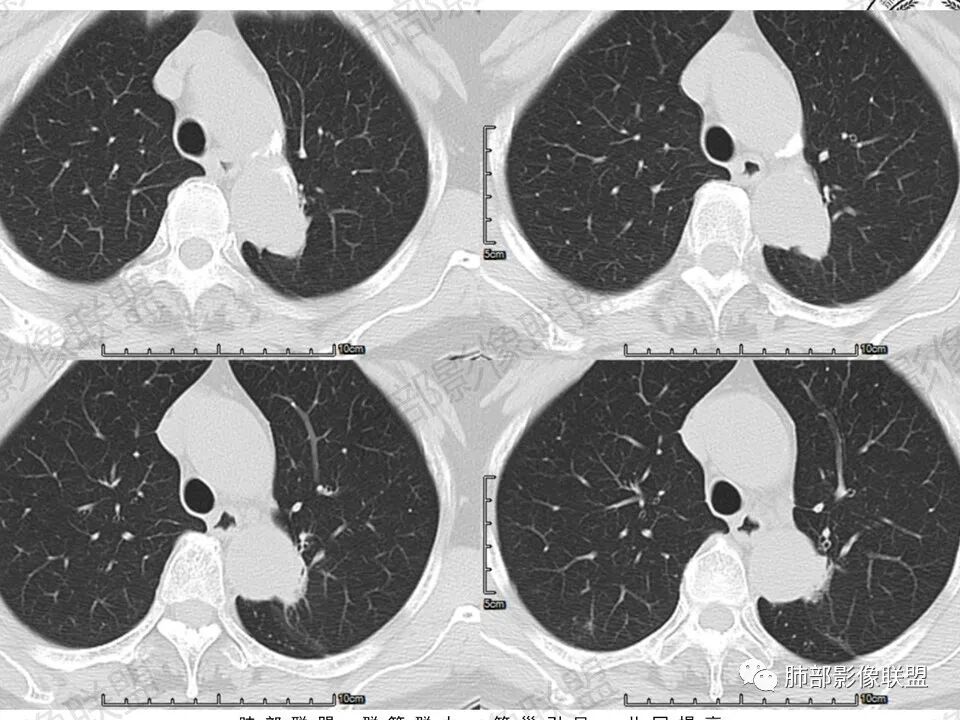

临床,眼科入院常规,肺部无症状,慢性炎症或恶性偷袭。视物变形,黄斑裂空可以解释,颅内不一定有问题,常规眼部ct,以防万一。定位,肺内血管进入,外缘毛糙,有肺纹进入,肺内的可能大。影像:    良性征像, 1、 病灶紧贴主动脉的细、长条状,炎性的王牌。2  、有直边、多边征 3、 矢状位略成梯形,垂直主动脉弓。  恶性征像较多,但多位低权重征像部分似是而非:1 主动脉弓后缘动脉壁似有侵袭 2  斜裂有轻度收缩 3 内上似见一个月牙铲 4 实性病灶周围有境界清晰的磨玻璃影  5 有小叶间隔阻挡现象 6 血管造影征?7 病灶略有膨隆 。中立征像:持续高强化,可以见于1 腺癌 、2 纤维类肿瘤 3肉芽肿病变。综上 1 腺癌第一(伴粘液腺)2 炎性肉芽肿待除外

马春平(张家港市一院胸外科):沿着支气管、肺动脉或主动脉、心缘、膈肌旁生长的腺癌形态会千奇百怪,抓住最重要的一条:找周边沿腺泡囊生长、边界较清的磨玻璃灶。

Coke with ice:病例收缩力偏弱,有磨玻璃,有牵拉支气管扩张,明显强化。可疑栽桩。符合实体型腺癌的表现。需要考虑到粘液腺的可能性。

尘缘:病灶沿主动脉匍匐样生长,但整体明显膨隆,胸膜牵拉凹陷,局部有小喇叭口样改变。

尘缘:边界清楚的GGO。

尘缘:局部血管增粗,扭曲

尘缘:局部有淋巴管增粗,小叶间隔增厚,提示癌淋可能。

尘缘:最后就是强化,虽然是明显渐进性强化,要考虑炎性可能,但腺癌明显渐进性强化的并不少见。

2.轴位显示主动脉弓旁依势傍行弧形高密度影,隐约见尖后段支气管进入并截止。病灶边界较清楚,见血管结构及线性影与邻近肺组织相延伸。

3.病灶渐进性显著均匀强化!动脉期未见主动脉腔异常通道。

4.冠矢状位病灶于弓上部偏后局限性“贝雷帽”状突起,提示病灶有局部膨隆特点,且病灶上份及后份饰以边缘较清楚磨玻璃影。